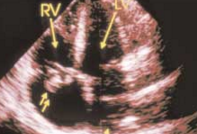

High-grade fever, chills, fatigue, malaise, and anorexia developed in a 35-year-old man following subclavian catheterization because of chronic renal failure of unknown cause.